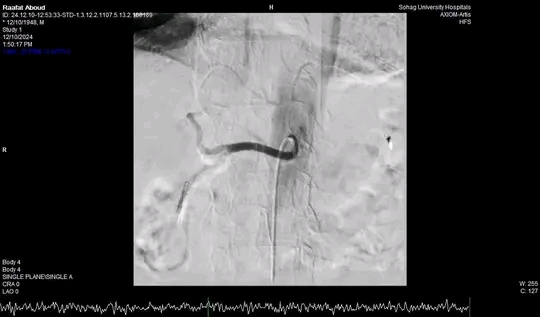

وأضاف الدكتور أحمد كمال المدير التنفيذي للمستشفيات الجامعية انه بعد اجراء الفحوصات للمريض تبين وجود قرحة كبيرة بالاثني عشر وشريان نازف، حيث نجح الفريق في التحكم المبدئي بالنزيف عن طريق تركيب مشبك معدني بالمنظار وحقن للقرحة النازفة، ثم تم استدعاء فريق أطباء وحدة الاشعة التداخلية علي الفور وتم عمل غلق للشريان النازف بشكل عاجل من خلال جهاز القسطرة.

وأوضح الدكتور محمد زاكي رئيس قسم الأشعة أن مثل هذه الحالات تعد من الطوارئ الطبية الخطيرة والتي تستوجب عمل قسطره شريانية عاجلة لغلق الشرايين النازفه مشيراً أن وحدة الأشعة التداخلية تم تزويدها بجهاز أشعه محوري متقدم لاجراء مثل هذه الحالات، وأن هذا النجاح هو نتيجة لتعاون أقسام المستشفي مع وحدة الأشعة التداخليه لتقديم خدمة مميزه للمرضي.